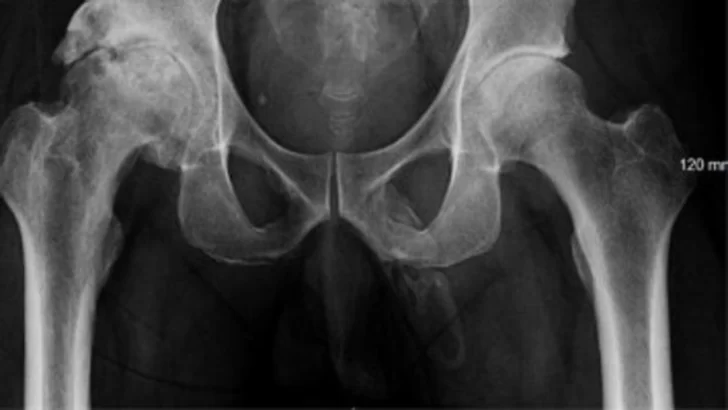

El examen físico fue negativo excepto por un dolor en el pene. Una radiografía pélvica realizada para descartar cualquier fractura mostró cambios degenerativos severos y asimétricos de la cadera derecha. También reveló una extensa calcificación en forma de placa a lo largo del pene. Se sospechó el diagnóstico de osificación del pene a lo largo de todo el eje del pene.